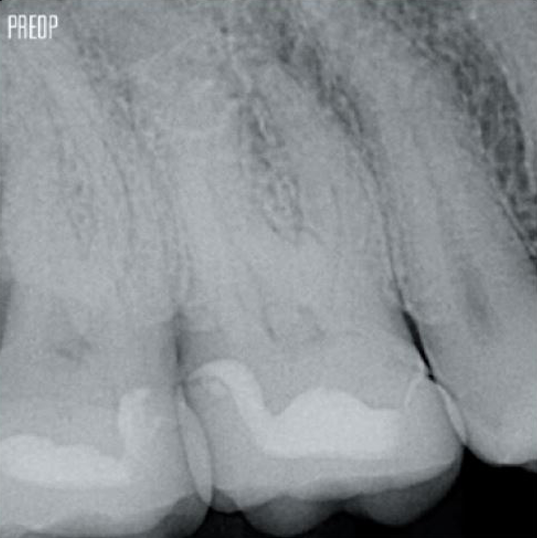

Foto's met dank aan dr. Ahmed Salman

Meer dentine behouden. Goede vormgeving, irrigatie en obturatie verzekerd.